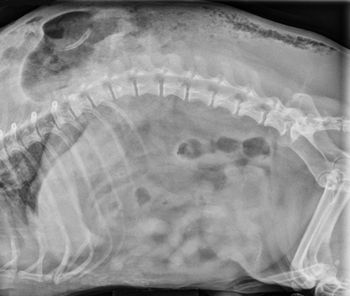

Pick the right diagnostic step in this senior dog.

When you have a patient with a hepatic vascular abnormality, how do you confirm it?

Add a little contrast to help you find your diagnosis.

Examine the imaging results to help solve this pug's problem.